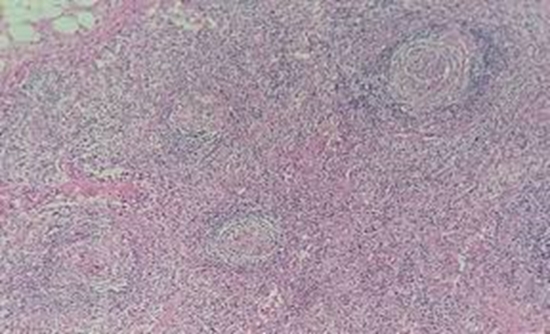

Castleman’s disease (CD) is characterized by non-neoplastic lymph node hyperplasia, and may be localized in a single lymph node (unicentric) or occurs systemically (multicentric). Nowadays, multicentric CD is most commonly observed in individuals infected with human immunodeficiency virus (HIV) type 1, in association with Kaposi’s sarcoma. Histopathologic and immunohistochemical evaluation of excised lymph node as well as imaging modalities, such as computed tomography (CT) and magnetic resonance imaging, are required for the diagnosis of CD.

We present a case of 46-year-old HIV-infected woman with fever, weakness, weight loss, and splenomegaly in the past 18 months. On physical examination, pale conjunctiva, jaundice, multiple cervical, inguinal, and axillary lymphadenopathies as well as hepatosplenomegaly were detected. Chest CT scan showed alveolar opacity in the lower lobe of the right lung and multiple lymph nodes in the mediastinum and bilateral perivascular, cervical, and axillary areas. Abdominopelvic CT scan showed huge splenomegaly, hepatomegaly, and multiple bilateral para-aortic, celiac, and inguinal lymphadenopathies, which were further confirmed as CD in pathological examination.